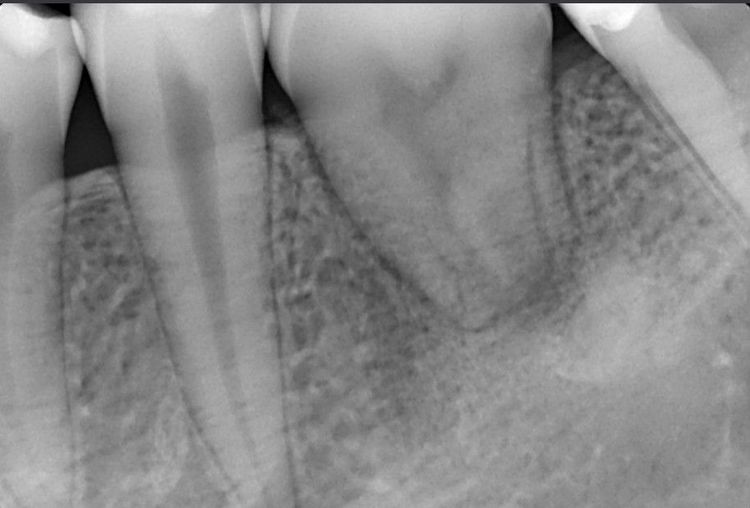

Зуб 3.6 - коронка значительно разрушена, на КЛКТ видим, что каналы зуба раньше лечили, но все равно результат неудовлетворительный: имеется патологическая резорбция дистального корня и очаг инфекции вокруг корней.

Через 20 дней шину сняли — зуб хорошо прижился. Спустя два месяца он уже полноценно участвовал в жевании, а снимки показывали стабильную и правильную адаптацию.